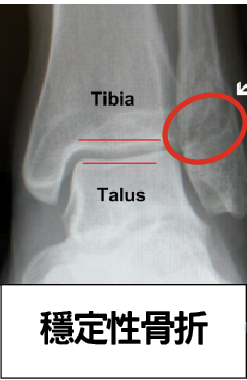

穩定性骨折: 若X光片上只見一條黑色骨裂線,而骨頭位置沒有移位(如下圖),多屬穩定性骨折。